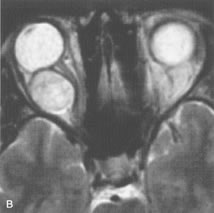

PATIENT PREPARATION Before MRI is performed, patients must be screened and prepared to avoid the potential hazards associated with the strong magnetic field. Patients who have ferrous aneurysm clips or cardiac pacemakers, who depend on life-support equipment, or who retain a possible metallic intraocular foreign body are not candidates for this imaging modality. MRI cannot be performed on obese patients who cannot fit into the bore of the magnet. Patients who are claustrophobic may not tolerate a prolonged period of study within the confines of the magnet, whereas others might do well if given a mild sedative. All worn metallic objects (e.g., necklaces, watches) should be taken off, credit cards set aside, and eye makeup removed before entering the room containing the magnet.5,20,34,35,36 NORMAL ORBITAL ANATOMY T1-weighted images provide the best anatomic details of the orbit because they display superior contrast resolution between normal structures (see Fig. 8). The vitreous has a long T1, resulting in an intermediate signal similar to brain, whereas the crystalline lens and sclera appear dark because of a longer T1 and short T2. The extraocular muscles, like all skeletal muscles, demonstrate a moderately long T1 and short T2 and highly contrast with the intense signal of the surrounding orbital fat (adipose tissue has an extremely short T1). The lacrimal glands appear as mottled areas of reduced intensity of the signal from the orbital fat in the lacrimal fossa. The optic nerves are seen with the same signal intensity as brain white matter and are hypointense relative to the orbital fat because their Tl is longer than the Tl of fat but shorter than the Tl of water. Cortical bone is not well delineated because it contains little free water, yielding minimal signal in MRI, and thus appears dark on all pulse sequences. This feature explains why MR images of the orbital apex and intracanalicular portion of the optic nerves are superior to comparable CT scans. Partial volume averaging of the bones in these regions obscures soft tissue details on CT images, whereas MRI reveals the signals only from the soft tissue structures with no cortical bone input. Bone marrow, on the other hand, is seen as a relatively intense signal because of its high fat content (see Fig. 8).37,38 T2-weighted pulse sequences are not ideal for imaging normal anatomy; however, they are particularly useful in revealing pathologic conditions (see Fig. 9). T2-weighted studies are most easily recognized by a bright vitreous signal. ORBITAL DISEASES Vascular Lesions Cavernous hemangiomas appear as well-circumscribed, smooth, usually intraconal masses that are isointense to muscle on T1-weighted images and hyperintense on T2-weighted images (Fig. 12). Patchy early enhancement is typically followed by diffuse, more homogeneous enhancement.39 The internal architecture of the mass, including septation and internal vasculature, may often be appreciated with high-quality orbital imaging.40 Lymphangiomas consist of ectatic vascular channels within a connective tissue stoma with varying degrees of lymphoid cellularity. On MRI, these tumors are typically poorly circumscribed, multicompartmental, and heterogeneous, often showing cystic dilations with fluid levels (Fig. 13). The signal characteristics within lymphangiomas vary considerably, reflecting cystic and solid components and the varying paramagnetic characteristics of blood at different stages of degradation.40–42 Acute hemorrhage appears hypointense on both T1- and T2-weighted formats. Methemoglobin present in subacute hemorrhage (3 to 14 days) leads to hyperintense signal on both T1- and T2-weighted images.41 A small percentage of lymphangiomas appear radiologically indistinct from orbital cavernous hemangiomas.43 Orbital varices are venous malformations that expand with increased systemic venous pressure, such as with Valsalva maneuvers. Because rapid acquisition of images during a Valsalva maneuver is important in imaging such a lesion, conventional or spiral CT is currently the modality of choice.44 MRI is an excellent modality for demonstrating enlargement of the cavernous sinus and dilation of the superior ophthalmic vein in patients with high-flow carotid-cavernous fistulas (Fig. 14).37MRA may be helpful in the evaluation of the venous outflow pattern. The rapidly flowing blood in these vascular structures carries the excited protons out of the section before they can be imaged, resulting in their dark appearance.5 In low-flow dural arteriovenous malformations, MRA may help define the arterial feeding vessels.45 Neural Lesions MRI is more effective than CT in delineating the intracranial optic nerves, chiasm, and optic tracts and, for this reason, is the preferred imaging modality in the evaluation of optic nerve disorders. The spatial relationships and image contrast of the orbital tissues with intraorbital optic nerve tumors is comparable between the two imaging modalities. The normal nerve is isointense to brain and appears enlarged and kinked owing to infiltration of an optic nerve glioma on T1-weighted images. Gliomas appear hyperintense on T2-weighted images and may be heterogeneous owing to cystic areas within the tumor. Contrast enhancement is variable.46 Intraorbital and intracranial optic nerve sheath meningiomas are usually isointense to cortical gray matter on Tl-weighted images and remain isointense on proton density studies (Fig. 15). Gd-DTPA is useful in delineating the intracranial extension of optic nerve meningiomas.7,47 The hyperostosis of bone and calcification associated with meningiomas are not demonstrated as well on MRI studies as on CT scans.20,37 Gd-DTPA–enhanced MRI also appears promising in the study of the permeability of the blood–brain barrier in selected optic neuropathies.22,48 MRI may reveal an enlarged optic nerve and some degree of contrast enhancement in cases of optic neuritis.49 Muscle Disorders Extraocular muscle enlargement in patients with thyroid-associated orbitopathy is demonstrated equally well with CT and MRI studies. However, the superior tissue contrast on MR images reveals better details of the relationships of the optic nerve to the thickened muscles at the orbital apex (Fig. 16).50 In addition, MRI may be able to differentiate between muscles that are enlarged as a result of edema and active inflammation and those enlarged because of fibrosis by their T2 relaxation times.21 Quantitative MRI was not found to be accurate in predicting the success of low-dose orbital irradiation.51 However, a muscular index relating the diameters of the rectus muscles to the bony orbital dimensions was useful in predicting optic nerve compression.52 MRI is also effective in imaging orbital tumors of mesenchymal origin, such as rhabdomyosarcoma, particularly in the assessment of extension into the anterior and middle cranial fossae (Fig. 17).37 The lack of any pathognomonic radiologic features necessitates rapid orbital biopsy when rhabdomyosarcoma is suspected. Osseous Lesions In general, CT is the imaging modality of choice when details of quantity and quality of bone are needed; however, abnormalities of bones can be detected indirectly by MRI. Cortical bone appears black (signal void) on MR images because of its low proton density and free-water content. The absence or discontinuity of the signal void of the orbital walls may represent bony destruction or fracture. Hyperostosis associated with prostate metastases or meningioma is visualized as areas of black smudging.50,53 Diseases in which the bone is replaced by pathologic tissues with a high free-water content, such as fibrous dysplasia, are well demonstrated on MRI. An intermediate signal intensity on T1-weighted images and hypointense signal on T2-weighted images is representative of fibrous dysplasia. Enhancement on post–Gd-DTPA MR scans is seen and is more evident in areas that are less mineralized.54 Cystic Lesions Dermoid cysts appear as rounded, well-defined lesions typically contiguous with an orbital bony suture. The high-intensity signal on T1-weighted images is attributed to the sebaceous-produced lipid contents (Fig. 18).31,50 Mucoceles may demonstrate a hypointense or hyperintense signal on MR images, depending on the concentration of proteinaceous or inflammatory fluid components. The integrity of the bony walls of the expanded sinus cavities cannot be assessed on MR as well as by CT.37,50,55,56 A high-signal intensity on Tl- and T2-weighted images is characteristic of orbital chronic hematic cysts because of the blood-breakdown products within the cysts.57 Trauma Although soft tissue relationships are usually better demonstrated on MRI, the evaluation of craniofacial bony trauma is preferable with CT. For example, prolapse of orbital fat through a fracture site and hemorrhage of adjacent tissues are demonstrated in an MR image, but the actual fractured bone is not imaged. Three-dimensional MRI of the orbit in subacute trauma has been described,58 although its precise role is not currently established. MRI has been suggested to be superior to CT in detecting intraorbital wooden foreign bodies.59,60 In a series of penetrating orbital injuries with organic foreign bodies, however, MRI was able to identify the foreign body in only four of seven cases.61 With an in vitro model for wood foreign body, McGuckin and colleagues concluded that CT was the imaging modality of choice.62 A careful history and, in selected cases, plain films to rule out a metallic foreign body are crucial before MRI is considered in patients with periocular trauma. MRI is particularly helpful in the detection and characterization of subperiosteal hematomas of the orbit (Fig. 19). They are most commonly seen in the subperiosteal space of the superior orbit as well-defined masses following a traumatic injury. The signal intensity varies depending on the acute, subacute, or chronic nature of the hematoma, based on the stage of blood degradation. Fresh hemorrhages are hypointense on T1-weighted images and hyperintense on T2 images. Hematomas that are 1 to 7 days old are hypointense on both T1- and T2-weighted images. T1-weighted images of hematomas more than a week old are hyperintense due to the oxidation of deoxyhemoglobin to methemoglobin, whereas the T2 images remain hypointense.63 Metastatic Tumors Breast carcinoma metastatic to the orbit has been demonstrated to be hypointense to the surrounding orbital fat on T1-weighted studies and hyperintense on T2-weighted images and has an affinity to the extraocular muscles (Fig. 20).50,64 The MRI characteristics of prostate carcinoma metastatic to the orbit have been described as involving the greater and lesser wing of the sphenoid, orbital roof, and optic canal. Diffuse bone hypertrophy with isointense or slightly hyperintense tissue on T1-weighted images represents the osteoblastic carcinomatous bone infiltration. Contrast enhancement is variable on T1-weighted and fat-suppressed images.65 Most other metastatic tumors also have a lower intensity signal on T1-weighted images and appear to displace or infiltrate normal orbital structures; however, their signal characteristics are variable on T2-weighted MR images.66 Many metastatic tumors demonstrate bright contrast enhancement with Gd-DTPA. Infectious Disorders MRI findings of preseptal and orbital cellulitis typically include increased signal intensities on T2-weighted images of the eyelids and orbital fat, respectively, due to the increased water content of the tissues. Since most cases of bacterial orbital cellulitis are associated with paranasal sinusitis, hyperintense signals of the affected sinuses may also be found on T2-weighted images as well as enhancement of polyps and granulation tissue on postgadolinium T1-weighted MR images. Subperiosteal abscess formation may occur due to contiguous spread of infection from the paranasal sinuses and appear on MRI as an area of intermediate signal on T1-weighted and proton-weighted MR images. The abscess may appear slightly hyperintense compared with muscle on T2-weighted scans with the necrotic contents having the greatest intensity.67 MRI and MRV are more sensitive than CT in revealing cavernous sinus thrombosis. Engorgement of the cavernous sinus, extraocular muscles, and ophthalmic veins is seen with hyperintensity of the thrombosed sinuses evident on all pulse sequences. The enlarged, thrombosed superior ophthalmic vein appears less hypointense than the normal contralateral ophthalmic vein, and hyperintensity within the lumen of the vessel may be seen on T1- and T2-weighted MR images.68 Inflammatory and Lymphoproliferative Lesions Inflammatory conditions of the orbit, both idiopathic (inflammatory pseudotumor) and those of known causes, have been found to be hypointense to fat and isointense to muscle on Tl-weighted studies and isointense or slightly hyperintense to fat on T2-weighted images (Fig. 21).50,64,69 The more fibrous or sclerosing varieties have less signal intensity on T2-weighted images. Marked enhancement is seen in pseudotumor infiltrates after gadolinium administration.70 The same signal characteristics are demonstrated in patients with Tolosa-Hunt syndrome, with mass lesions seen in the cavernous sinuses and orbital apices.71 Lymphomas have MRI characteristics similar to those of inflammatory lesions in that they are hypointense to fat and isointense to muscle on T1-weighted images (Fig. 22). They may appear hyperintense to fat on T2-weighted images, perhaps owing to less fibrosis than that seen in orbital inflammatory pseudotumor, although this is not a consistent finding.31,50,66 Lymphoid tumors typically enhance moderately after contrast injection. Unfortunately, studies have shown that tumor density and homogeneity are similar between inflammatory and malignant orbital infiltrates, and MRI cannot differentiate these lesions.72,73 Lacrimal Gland Tumors Lacrimal gland lesions present special problems in diagnosis and management. Pleomorphic adenoma (benign mixed tumor) should not be biopsied, but rather excised in toto. On the other hand, for lymphoma and inflammatory infiltrates, incisional biopsy is more appropriate than complete excision of the lacrimal gland. Thus, preoperative clinical and radiologic evaluation are especially crucial in planning appropriate surgical management. Pleomorphic adenomas demonstrate long T1 and T2 signal characteristics. They may show heterogeneity on T2-weighted images74 and moderate to marked enhancement with contrast.75 Signal characteristics of adenoid cystic carcinoma include hypointensity to fat on T1-weighted images, hyperintensity to fat with increased T2 weighting, and isointensity to fat on proton density-weighted studies (Fig. 23).31,75 Secondary bony alterations of the lacrimal fossa associated with lacrimal gland tumors, such as remodeling (benign mixed tumor) or destruction (adenoid cystic carcinoma), are seen indirectly on MR images; however, bone windows on CT scans provide better delineation of these changes. In contrast to the round or globular appearance of benign or malignant epithelial tumors of the lacrimal gland, lymphoproliferative tumors usually appear to be molding or draping onto the globe and the surrounding bony orbit. LACRIMAL DRAINAGE SYSTEM DISORDERS MRI with surface coils provides excellent spatial resolution and tissue-specific signal intensities of the lacrimal drainage system. These parameters have been found useful to more accurately demonstrate the extent of lesions in the lacrimal sac and differentiate long-standing mucoceles from solid tumors than CT.76 Physiologic studies in patients with tearing disorders now include MR dacryocystography, in which Gd-DTPA is either placed topically in the conjunctival fornix or injected by cannulation into the lacrimal sac. They provide a detailed morphologic and functional analysis of the lacrimal excretory system; however, they are no more sensitive than digital-subtraction dacryocystography or CT dacryocystography.77–79 INTRAOCULAR TUMORS On MRI, uveal melanomas have a typical appearance that helps to differentiate them from other primary and secondary intraocular tumors as well as choroidal detachments. Pigmented melanomas are hyperintense on Tl-weighted images, hypointense on T2-weighted studies, and hyperintense on proton density–weighted examinations (Fig. 24).30,31,50,80–82 These signal characteristics have been attributed to the paramagnetic properties of melanin because of stable free radicals that shorten the T1 and T2 relaxation times. Moderate enhancement is seen on postgadolinium T2-weighted images. Gadolinium-enhanced T1-weighted images are particularly sensitive in detecting choroidal melanomas.83 MRI may be less sensitive in detecting extrascleral extension of tumor than echography performed by an experienced ultrasonographer.84 Tumors metastatic to the choroid are hyperintense on T1- and T2-weighted images.24 The signal characteristics, however, may be similar to those seen with choroidal melanoma. Choroidal hemangiomas, on the other hand, have an intermediate signal on T1-weighted sequences and become hyperintense on T2-weighted images50 as well as proton density–weighted images.81 Retinoblastomas display moderate signal intensity on T1-weighted studies and a low signal on T2-weighted images.31,80,85 Calcification can be easily detected by CT and ocular ultrasonography but is not imaged by MRI.25,50 The presence of optic nerve involvement is best evaluated by MRI. ACQUIRED ANOPHTHALMIA When an eye is removed owing to tumor or trauma, an implant is typically placed in the intraconal space. MRI may be useful in defining the size, shape, and position of such orbital implants.86 Porous hydroxyapatite or polyethylene implants are preferred by many surgeons performing enucleation or evisceration. A porous implant offers the possibility of supporting a motility coupling peg to increase the movement of the overlying prosthesis. MRI with contrast is used by some surgeons to evaluate the degree of fibrovascular ingrowth in hydroxyapatite87 and porous polyethylene88 implants prior to motility peg placement. |